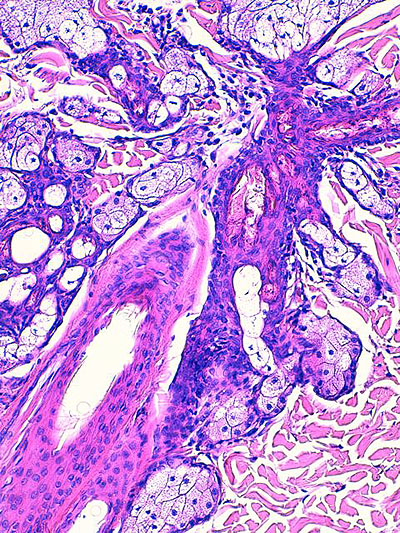

Photo 5 : (Hémalun-Eosine – X400) : Vue rapprochée d’un isthme folliculaire,

permettant de visualiser la plurilobulation “médusoïde” d’une glande sébacée,

l’hyperplasie et l’hyperkératose orthokératosique de son canal excréteur et

l’inflammation péri-isthmique lympho-plasmocytaire.

Légendes de la Photo 5 :

- Pointe de flèche rouge = lumière du canal sébacé hyperkératosique

- Étoile turquoise = paroi épithéliale hyperplasique du canal sébacé

- Carré rouge = lumière del’isthme follicualire

- Étoile rouge = lobules d’une glande sébacée hyperplasique

- Étoile rouge = infiltrat inflammatoire lympho-plasmocytaire péri-isthmique, le reste du derme n’est pas inflammatoire

Photo 6 : (Hémalun-Eosine – X400) : Vue rapprochée d’un canal sébacé

permettant de visualiser son hyperplasie et son hyperkératose orthokératosique,

la distension kystique de la glande sudorale épitrichiale et l’inflammation péri-isthmique

lympho-plasmocytaire et discrètement mural au sein de la paroi du canal sébacé.

Légendes de la Photo 6 :

- Étoile turquoise = paroi du canal sébacé hyperplasique

- Flèche double noire = lobules de glande sébacée

- Flèche double bleue = tige pilaire dans un isthme folliculaire

- Carré rouge = infiltrat inflammatoire lympho-plasmocytaire péri-isthmique pénétrant discrètement la paroi épithéliale du canal sébacé

- Étoile rouge = lumière du canal sébacé siège d’une hyperkératose orthokératosique

- Étoile noire = lumière kystique d’une glande sudorale épitrichiale (portion fundique)